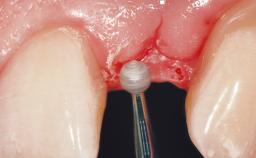

Late Flapless Placement of an Implant in a Maxillary Left Central Incisor Site

A 39-year-old male patient presented with a chief complaint of discomfort and gingival discoloration around his maxillary left central incisor. He was in good general health and was a non-smoker. His past dental history was significant because of the traumatic fracture of tooth 21 in a sporting accident at age 13. Initial dental treatment included endodontic therapy and a full-coverage restoration. The patient became symptomatic 5 years later, when structural failure of the tooth resulted in the dislodgment of the crown. Endodontic retreatment, apical surgery, and post-and-core restoration were performed.

Soft Tissue Grafting Simultaneous

Soft Tissue Contour and Volume Slightly compromised